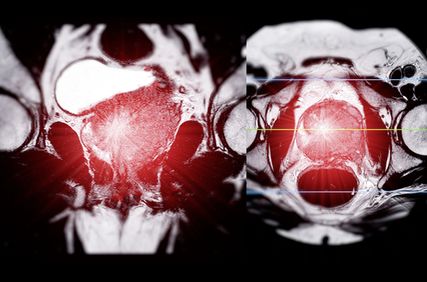

Therapiestrategien beim hormonsensitiven Prostatakarzinom

Die Therapielandschaft des fortgeschrittenen Prostatakarzinoms hat sich seit 2014 und damit der ersten Präsentation der CHAARTED-Studie praktisch jährlich verändert und erweitert. Heute stehen sehr viele und wirksame Therapieoptionen zur Verfügung.

Für Personen mit metastasiertem, hormonsensitivem Prostatakarzinom (mHSPC) ist mit der Präsentation der Studie AMPLITUDE am ASCO-Jahrestreffen 2025 eine zusätzliche neue Therapiemöglichkeit eröffnet worden. Diese Möglichkeit kommt infrage für Fälle des Nachweises von relevanten Alterationen in Genen, die in die homologe Rekombinationsreparatur involviert sind (BRCA1, BRCA2, BRIP1, CDK12, CHEK2, FANCA, PALB2, RAD51B, RAD54L).

Personen mit mHSPC und Nachweis der vordefinierten genomischen Alterationen wurden in der Studie auf ADT+Abirateron/Prednison ± den PARP-Inhibitor Niraparib randomisiert. Docetaxel für die mHSPC-Situation vor Studieneinschluss war erlaubt und wurde 16% der eingeschlossenen Personen verabreicht. Die AMPLITUDE-Studie hat für die Kombination mit dem zusätzlichen PARP-Inhibitor zum Zeitpunkt der Präsentation einen relevanten Vorteil im radiografisch progressionsfreien Überleben gezeigt, insbesondere bei Vorliegen einer BRCA1- oder BRCA2-Alteration (radiologisches progressionsfreies Überleben [rPFS]: nicht erreicht vs. 26 Monate; HR: 0,52; 95% CI: 0,37–0,72). In der Gesamtstudienpopulation konnte dieser Vorteil auch gezeigt werden (rPFS: nicht erreicht vs. 29,5 Monate; HR: 0,63; 95% CI: 0,49–0,80).3

Zum Zeitpunkt der Präsentation konnte kein signifikanter Gesamtüberlebensvorteil gezeigt werden, hier werden weitere Daten im Verlauf erwartet. Bislang fehlt eine Zulassung für die Kombinationstherapie analog der AMPLITUDE-Studie, aber für Personen mit metastasiertem Prostatakarzinom, insbesondere bei einer synchron metastasierten Situation und hoher Tumorlast und bei Nachweis einer BRCA1- oder BRCA2-Alteration, sollte diese Kombination in Betracht gezogen werden.